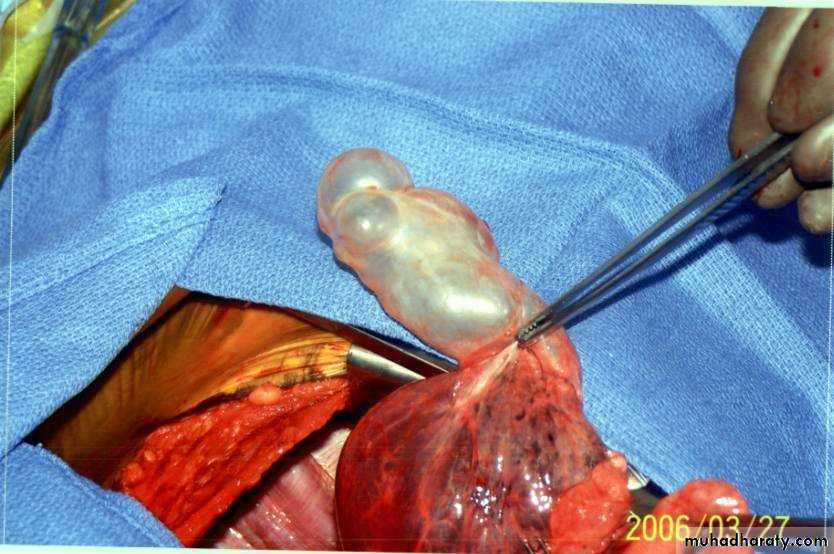

Surgical intervention

Bullectomy for younger patients in whom large bullae compress relatively normal lung tissuesLung volume reduction surgery (LVRS) for highly selected patients with;

*predominantly upper lobe emphysema

*normal gas transfer

*no pulmonary hypertension,

where peripheral emphysematous tissue is resected to reduce hyperinflation and the work of breathing